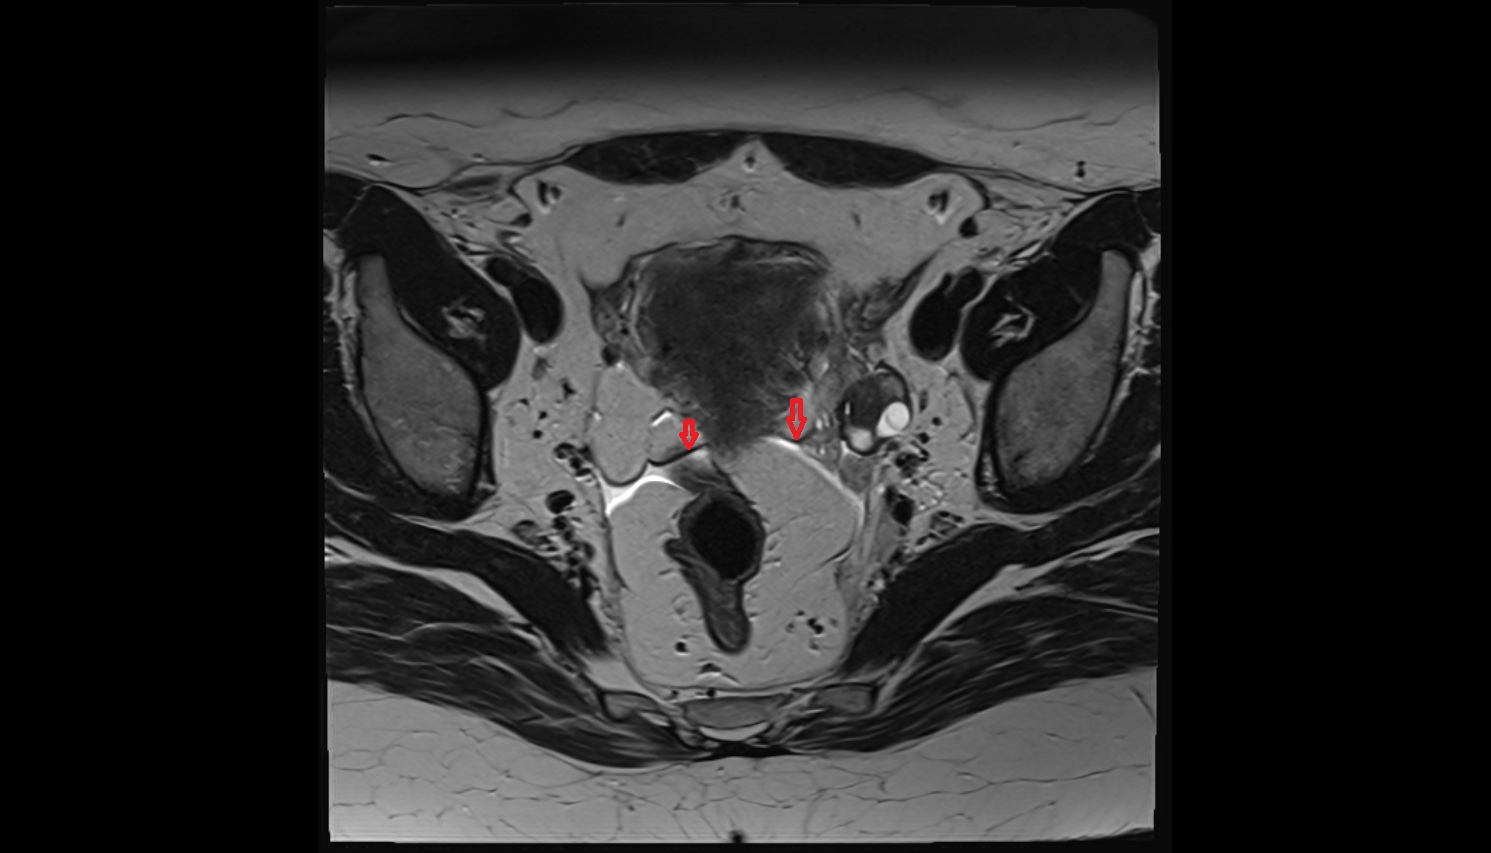

- Uterus

- Ovaries

- Right ovary

- Left ovary

- Fallopian tube